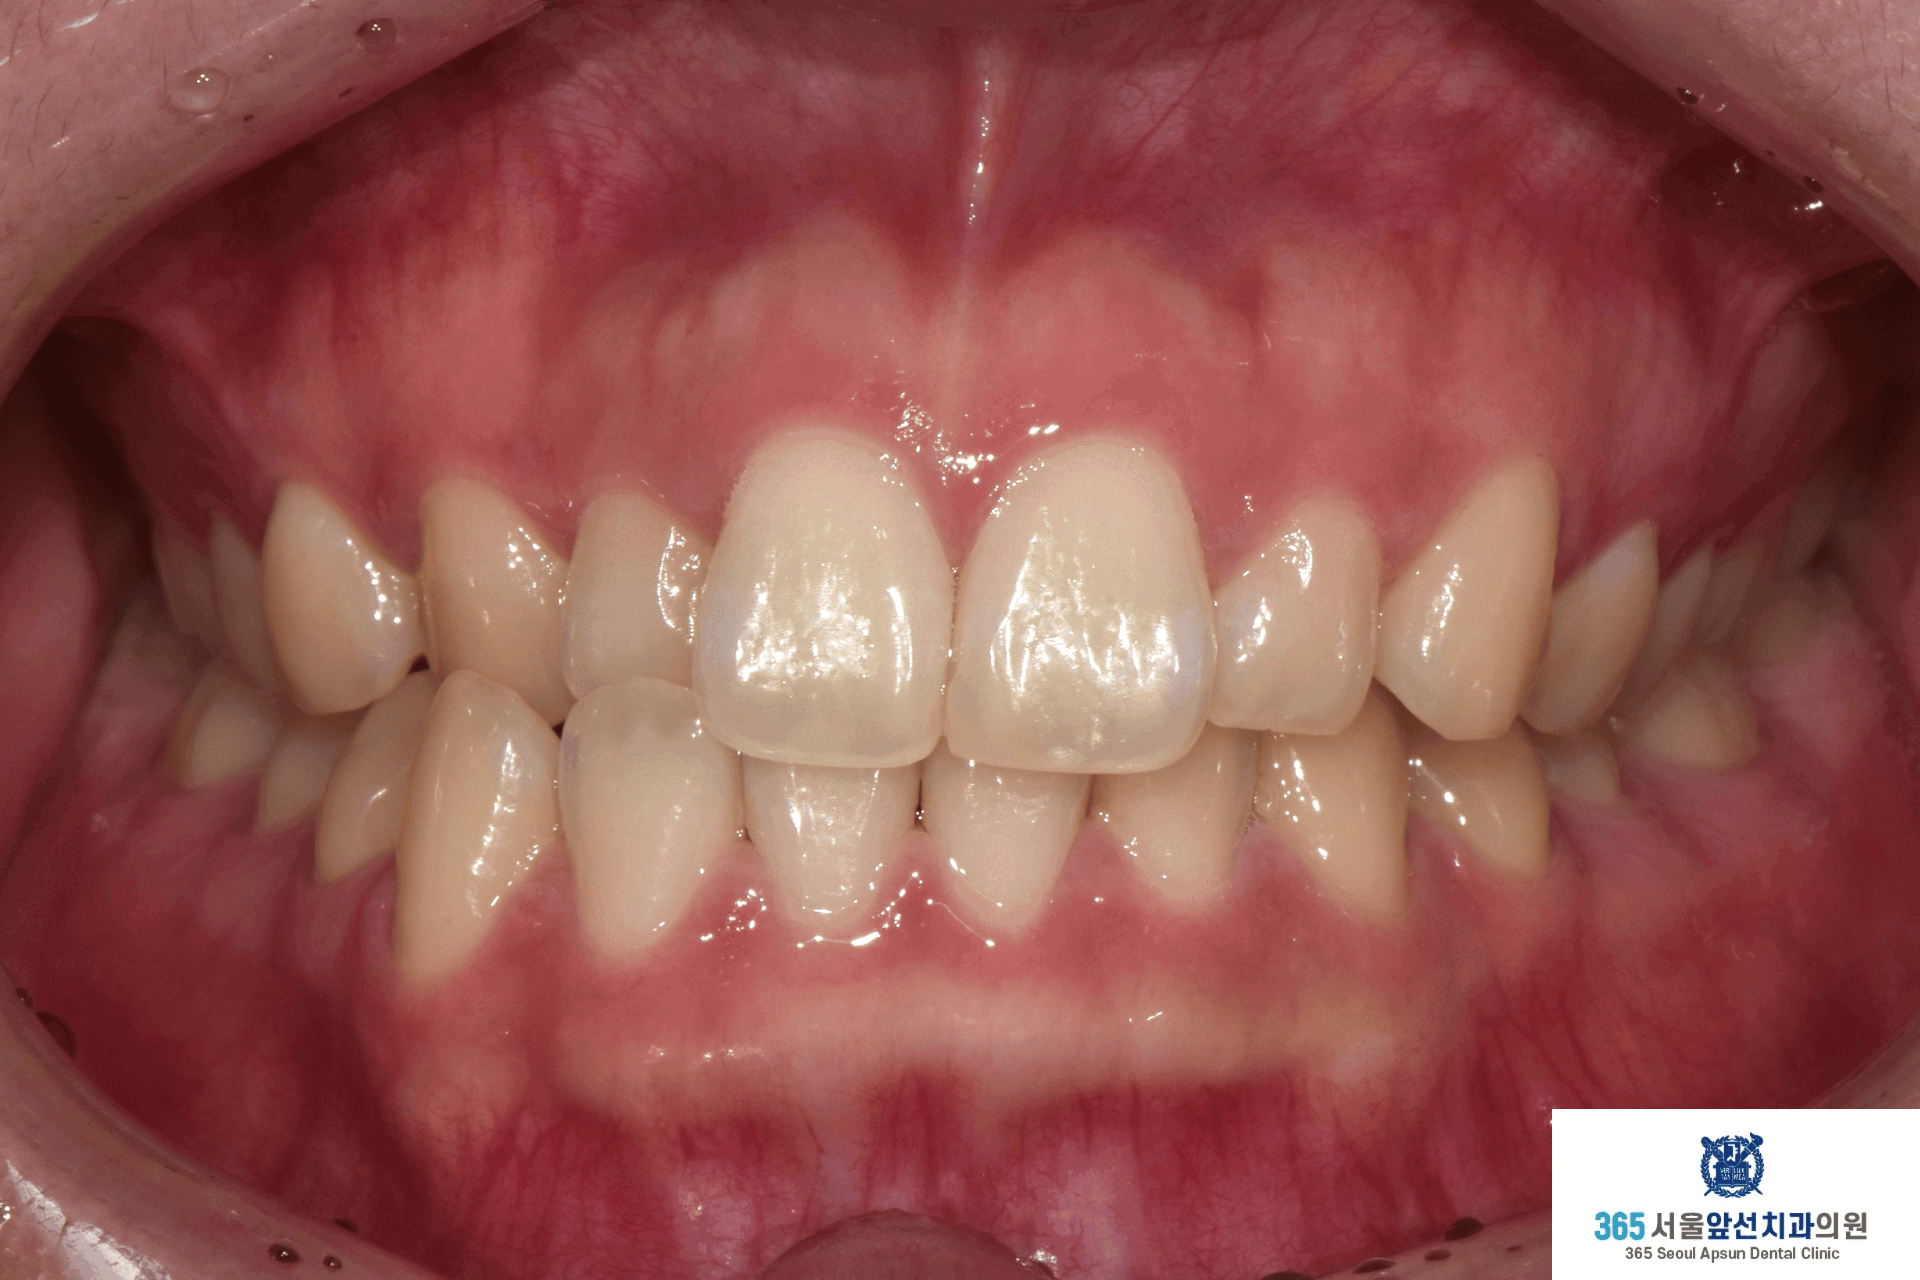

촬영일시 : 2024.10.23. 치료 전, 우측 측절치와 견치(송곳니)의 반대교합과 정중선 불일치가 관찰됩니다. 양측 상악 측절치가 5.6mm 폭경으로 왜소치 경향을 보이며 Bolton 의 전치부 비율이 86.73으로, 이상적인 윗니와 아랫니 앞니의 비율을 고려한 폭경에 비해 5.0mm가 부족합니다. 이 경우, 왜소치의 폭경을 키워 수복한다면 이상적인 교합을 형성할 수 있습니다. 해당 환자분께서는 왜소치의 수복 없이 치료하기를 원하셔서, 보상적으로 하악 치열의 폭경 감소와 Canine key compromise를 통해 최대한 심미적이고 기능적인 교합을 만들어드렸습니다.